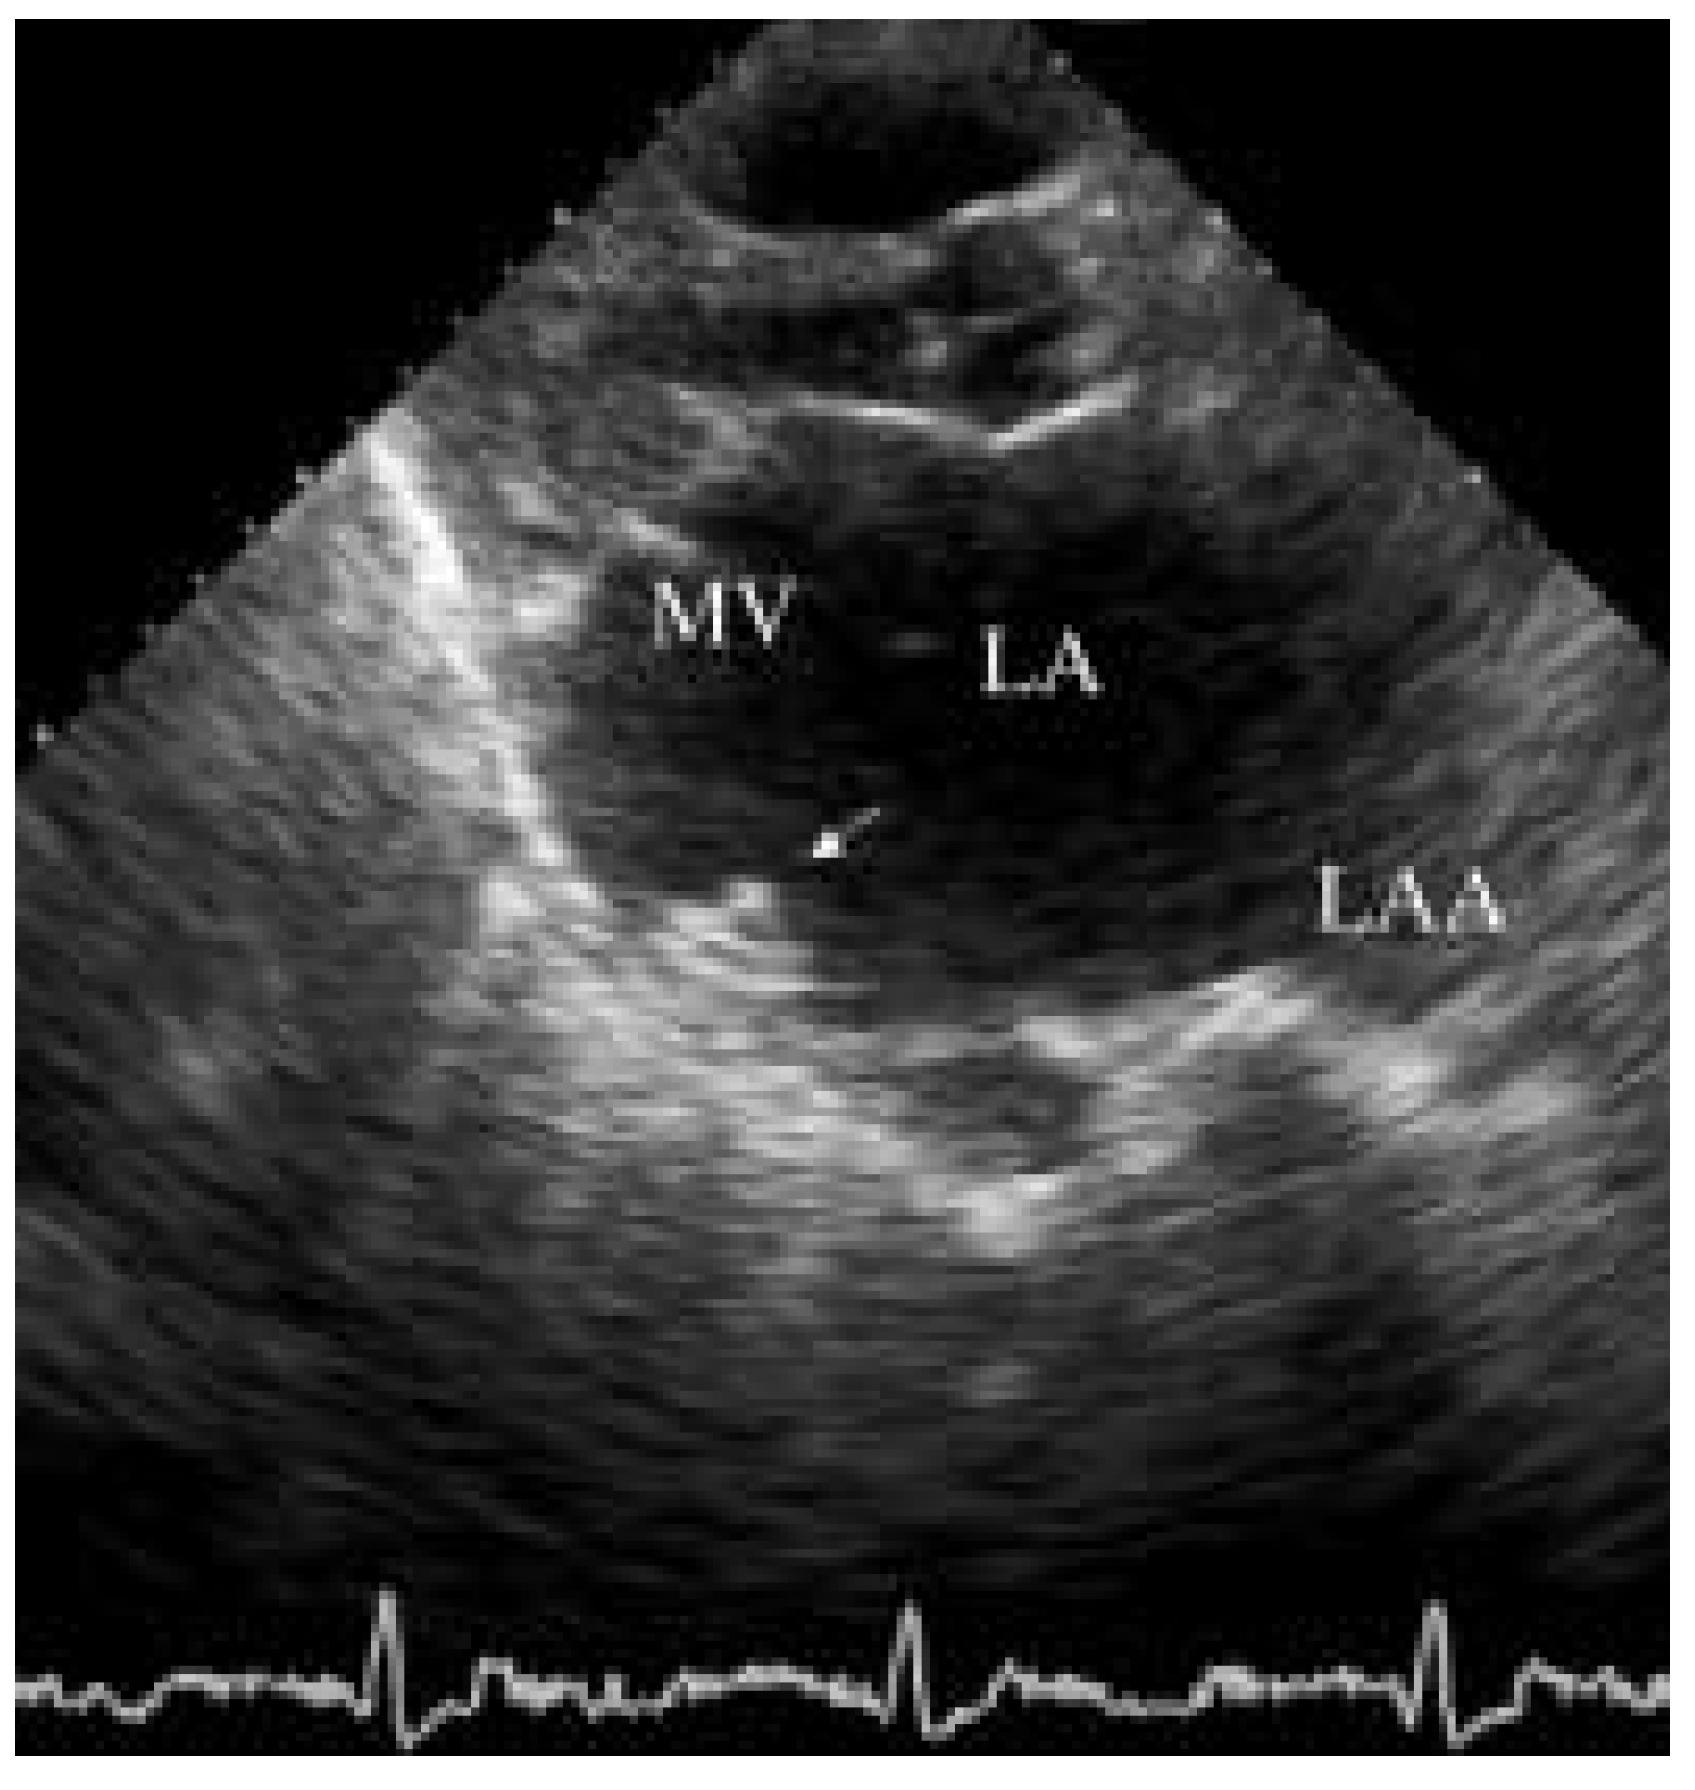

An 80-year-old woman with symptomatic rheumatic mitral valve disease and chronic atrial fibrillation was admitted for mitral valvuloplasty and interventional occlusion of the left atrial appendage. Mitral commissurotomy had been performed 30 years earlier. Because of unstable INR with warfarin therapy, she was at increased risk for bleeding and thromboembolism. The left atrium was grotesquely dilated (10.3 × 4.6 cm) and showed spontaneous echo contrast. Severe calcification of the mitral valve and mitral annulus resulted in significant stenosis (mitral valve area 1.0 cm2, mean pressure gradient 11 mm Hg) and mild mitral regurgitation. The coronary arteries were normal and mitral valvuloplasty was performed resulting in only moderate improvement with a valve area of 1.3 cm2. After fluoroscopic identification of the atypically located left atrial appendage by contrast medium injection, a 10 mm Amplatzer septal occluder was inserted (fig. 1A). However, after its detachment from the catheter, the device dislodged from the left atrial appendage and was found floating in the left atrium (fig. 1B, C). In light of the residual mitral stenosis with moderate regurgitation, no attempt was made to retrieve the dislodged device percutaneously. The patient was left with bed rest and heparin. The next day the device was still in the left atrium (fig. 2) and mitral valve replacement was performed. The occluder was removed from the left atrium and found clean from thrombosis (fig. 3). An atrial septal tear resulting from the transseptal puncture was repaired, and the left atrial appendage was obliterated. Postoperative recovery was uneventful.

Figure 2. Transthoracic echocardiogram. Amplatzer occluder (arrow) floating in the left atrium (LA). LAA = left atrial appendage; MV = mitral valve.